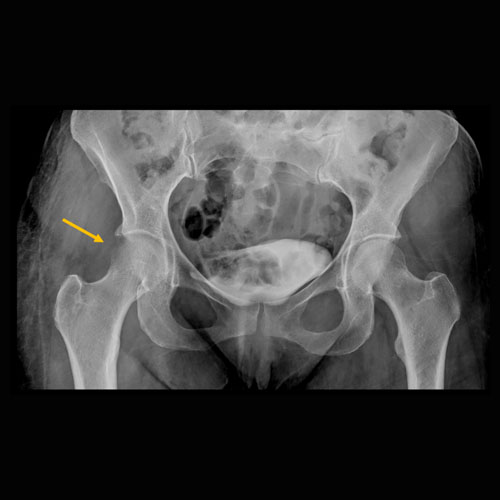

Foot pain after trauma.Exam

Soft tissue defect along the medial foot with possible underlying osteomyelitis of the first metatarsal head.

MRI to further evaluate for osteomyelitis.

Urgent (Action Necessary in a few hours)